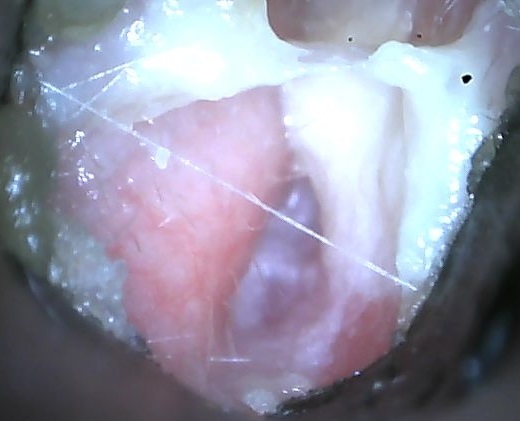

Otoskopische Untersuchung

Zu jeder allgemeinen Untersuchung gehört auch ein Blick in die Ohren mit dem Otoskop oder der Videokamera. Ganz besonders aufmerksam muss dies natürlich beim Verdacht auf eine Otitis erfolgen. Unter sanftem Zug am Ohr (nach "oben") werden die äußeren Gehörgänge und das Trommelfell inspiziert. Dabei wird auf Schwellungen, Rötungen, Ohrenschmalz, Eiter, Blut, Krusten, Milben und anderweitige Auffälligkeiten geachtet.

Da Milben lichtscheu sind, sollte bei einem entsprechenden Verdacht das Otoskop zunächst eingeführt und erst dann das Licht eingeschaltet werden. So kann der Tierarzt die Parasiten davonkrabbeln sehen. Wird das Otoskop mit bereits eingeschalteter Beleuchtung eingeführt, ziehen sich die Milben sofort zurück und sind oftmals mehr zu sehen.

Bei Widdern ist das Trommelfell aufgrund der sehr engen Gehörgänge und der Ansammlung von Zerumen (Ohrenschmalz) meist nicht einsehbar. Indem der Tierarzt es reinigt und anschließend erneut untersucht, kann der komplette Gehörgäng betrachtet werden.